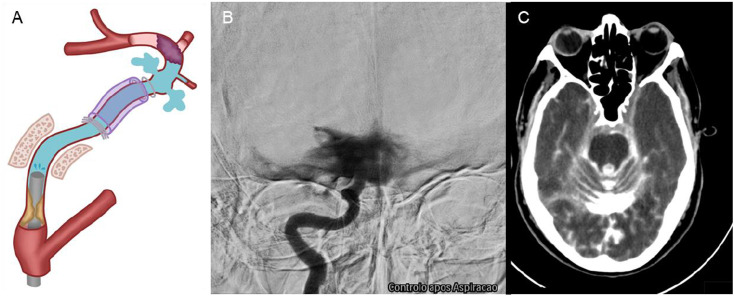

串联闭塞患者的血管内血栓切除术很少会导致颈内动脉破裂,从而引发蛛网膜下腔出血和死亡。然而,文献中很少报道和讨论这种并发症及其原因。我们描述了两例串联闭塞患者在血管内血栓切除术中发生颈内动脉破裂的病例。据推测,在再通之前,对远端病变的主要方法会造成盲区,在人工注射造影剂时会面临管腔内压力升高,超过血管的阻力,导致动脉壁破裂。为了防止这种并发症,有人提出了先治疗近端闭塞、通过微导管注入造影剂或将血管内支持导管缩回到颈内动脉狭窄近端等方法,并对这些方法进行了讨论。

Endovascular thrombectomy in patients with tandem occlusions can rarely result in the rupture of the internal carotid artery, leading to subarachnoid haemorrhage and death. However, this complication and its causes are rarely reported and discussed in the literature. We describe two cases of internal carotid artery rupture during endovascular thrombectomy in patients with tandem occlusion. It is hypothesised that the primary approach to the distal lesion, before recanalization, creates a blind alley that faces an intraluminal pressure increase upon manual contrast injection, surpassing the vessel's resistance and resulting in arterial wall rupture. To prevent this complication, approaches such as treating the proximal occlusion first, injecting the contrast through a microcatheter or retracting the endovascular support catheter proximally to the stenosis of the cervical internal carotid artery have been suggested and are discussed.